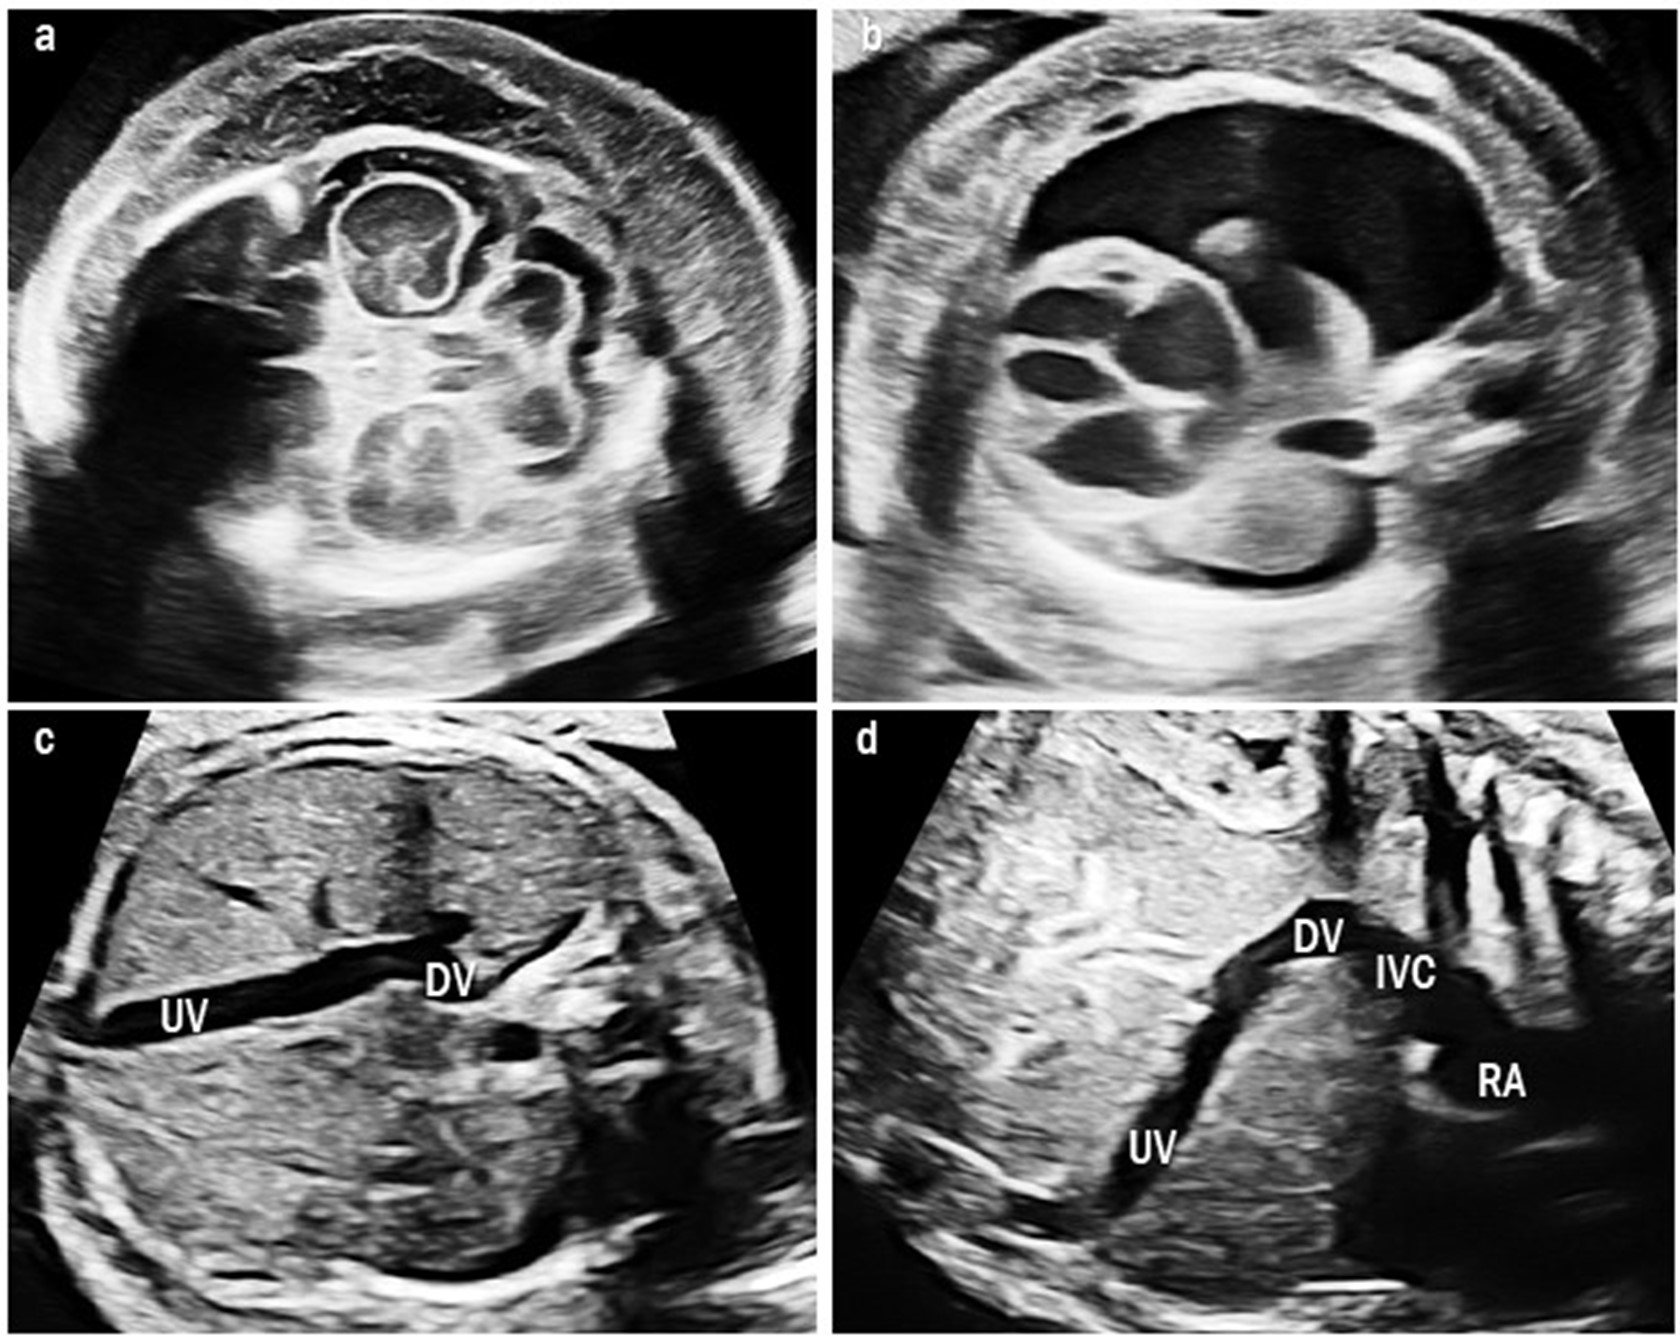

There were eight cases of type I UPSVS. These cases did not show any DV, and the UV was connected to the systemic vein. In six cases (cases 1, 4–8), the UV directly drained into the right atrium (Fig. 2). In two cases (cases 2 and 3), the UV drained into the inferior vena cava (IVC). All but one (7/8, 88%) were associated with other structural abnormalities: two cases with VACTERL association (cases 6 and 8), which included three or more combinations of vertebral defects (V), anal atresia (A), cardiac abnormalities (C), tracheoesophageal fistula (TE), renal abnormalities (R), and limb defect (L). And one case with Cornelia de Lange syndrome (case 3), which shows distinctive facial characteristics and growth delays [8]. The patient with trisomy 18 died at the age of seven months because of respiratory failure due to tracheomalacia (case 5). Cardiomegaly was observed in five fetuses, three of which resolved. The median GA at birth was 38.1 weeks (range, 33.3–39.4) and the median birth weight was 2540 g (range, 1910–2870). Five neonates had birth weights below the 10th percentile, and four of them were below the 3rd percentile.

Fig. 2.

Fig. 2.Two-dimensional color Doppler image of type I umbilical-portal-systemic venous shunt in case 7. Umbilical vein directly drains into the right atrium without going through the ductus venosus. RA, right atrium.

We found one case of type II UPSVS (case 9). The fetus had a short DV that drained into the IVC, but other structures of the umbilical-portal-DV complex were intact. The fetus showed cardiomegaly and fetal hydrops with severe skin edema and pleural effusion (Fig. 3). This fetus was confirmed to have a 3p deletion. The fetal hydrops resolved after birth. At the time of writing, the patient was 17 months old and had developmental delay.

Fig. 3.

Fig. 3.Ultrasound images of type II umbilical-portal-systemic venous shunt in case 9. The fetus showed severe fetal hydrops: (a) severe skin edema and (b) pleural effusion. (c) Transverse abdominal image shows the UV connected to the DV and it drains at the lower site than usual. (d) Sagittal image shows a short DV draining into the IVC below the diaphragm. UV, umbilical vein; DV, ductus venosus; IVC, inferior vena cava; RA, right atrium.